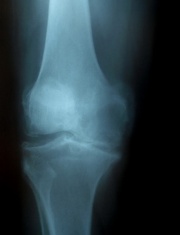

L’arthrose du genou est appelée gonarthrose. Elle n’atteint pas nécessairement les cartilages des trois os en même temps.

• l’arthrose fémoro-tibiale, comme le dit son nom, se situe entre le fémur et le tibia. C’est la plus courante des arthroses du genou. Elle est le plus souvent due à une déviation de l'axe de la jambe.

• l'arthrose située entre le fémur et la rotule (arthrose fémoro-patellaire) est presque aussi fréquente. Elle fait souvent suite à un traumatisme, à une instabilité de la rotule ou un à déséquilibre de force dans les muscles du genou.